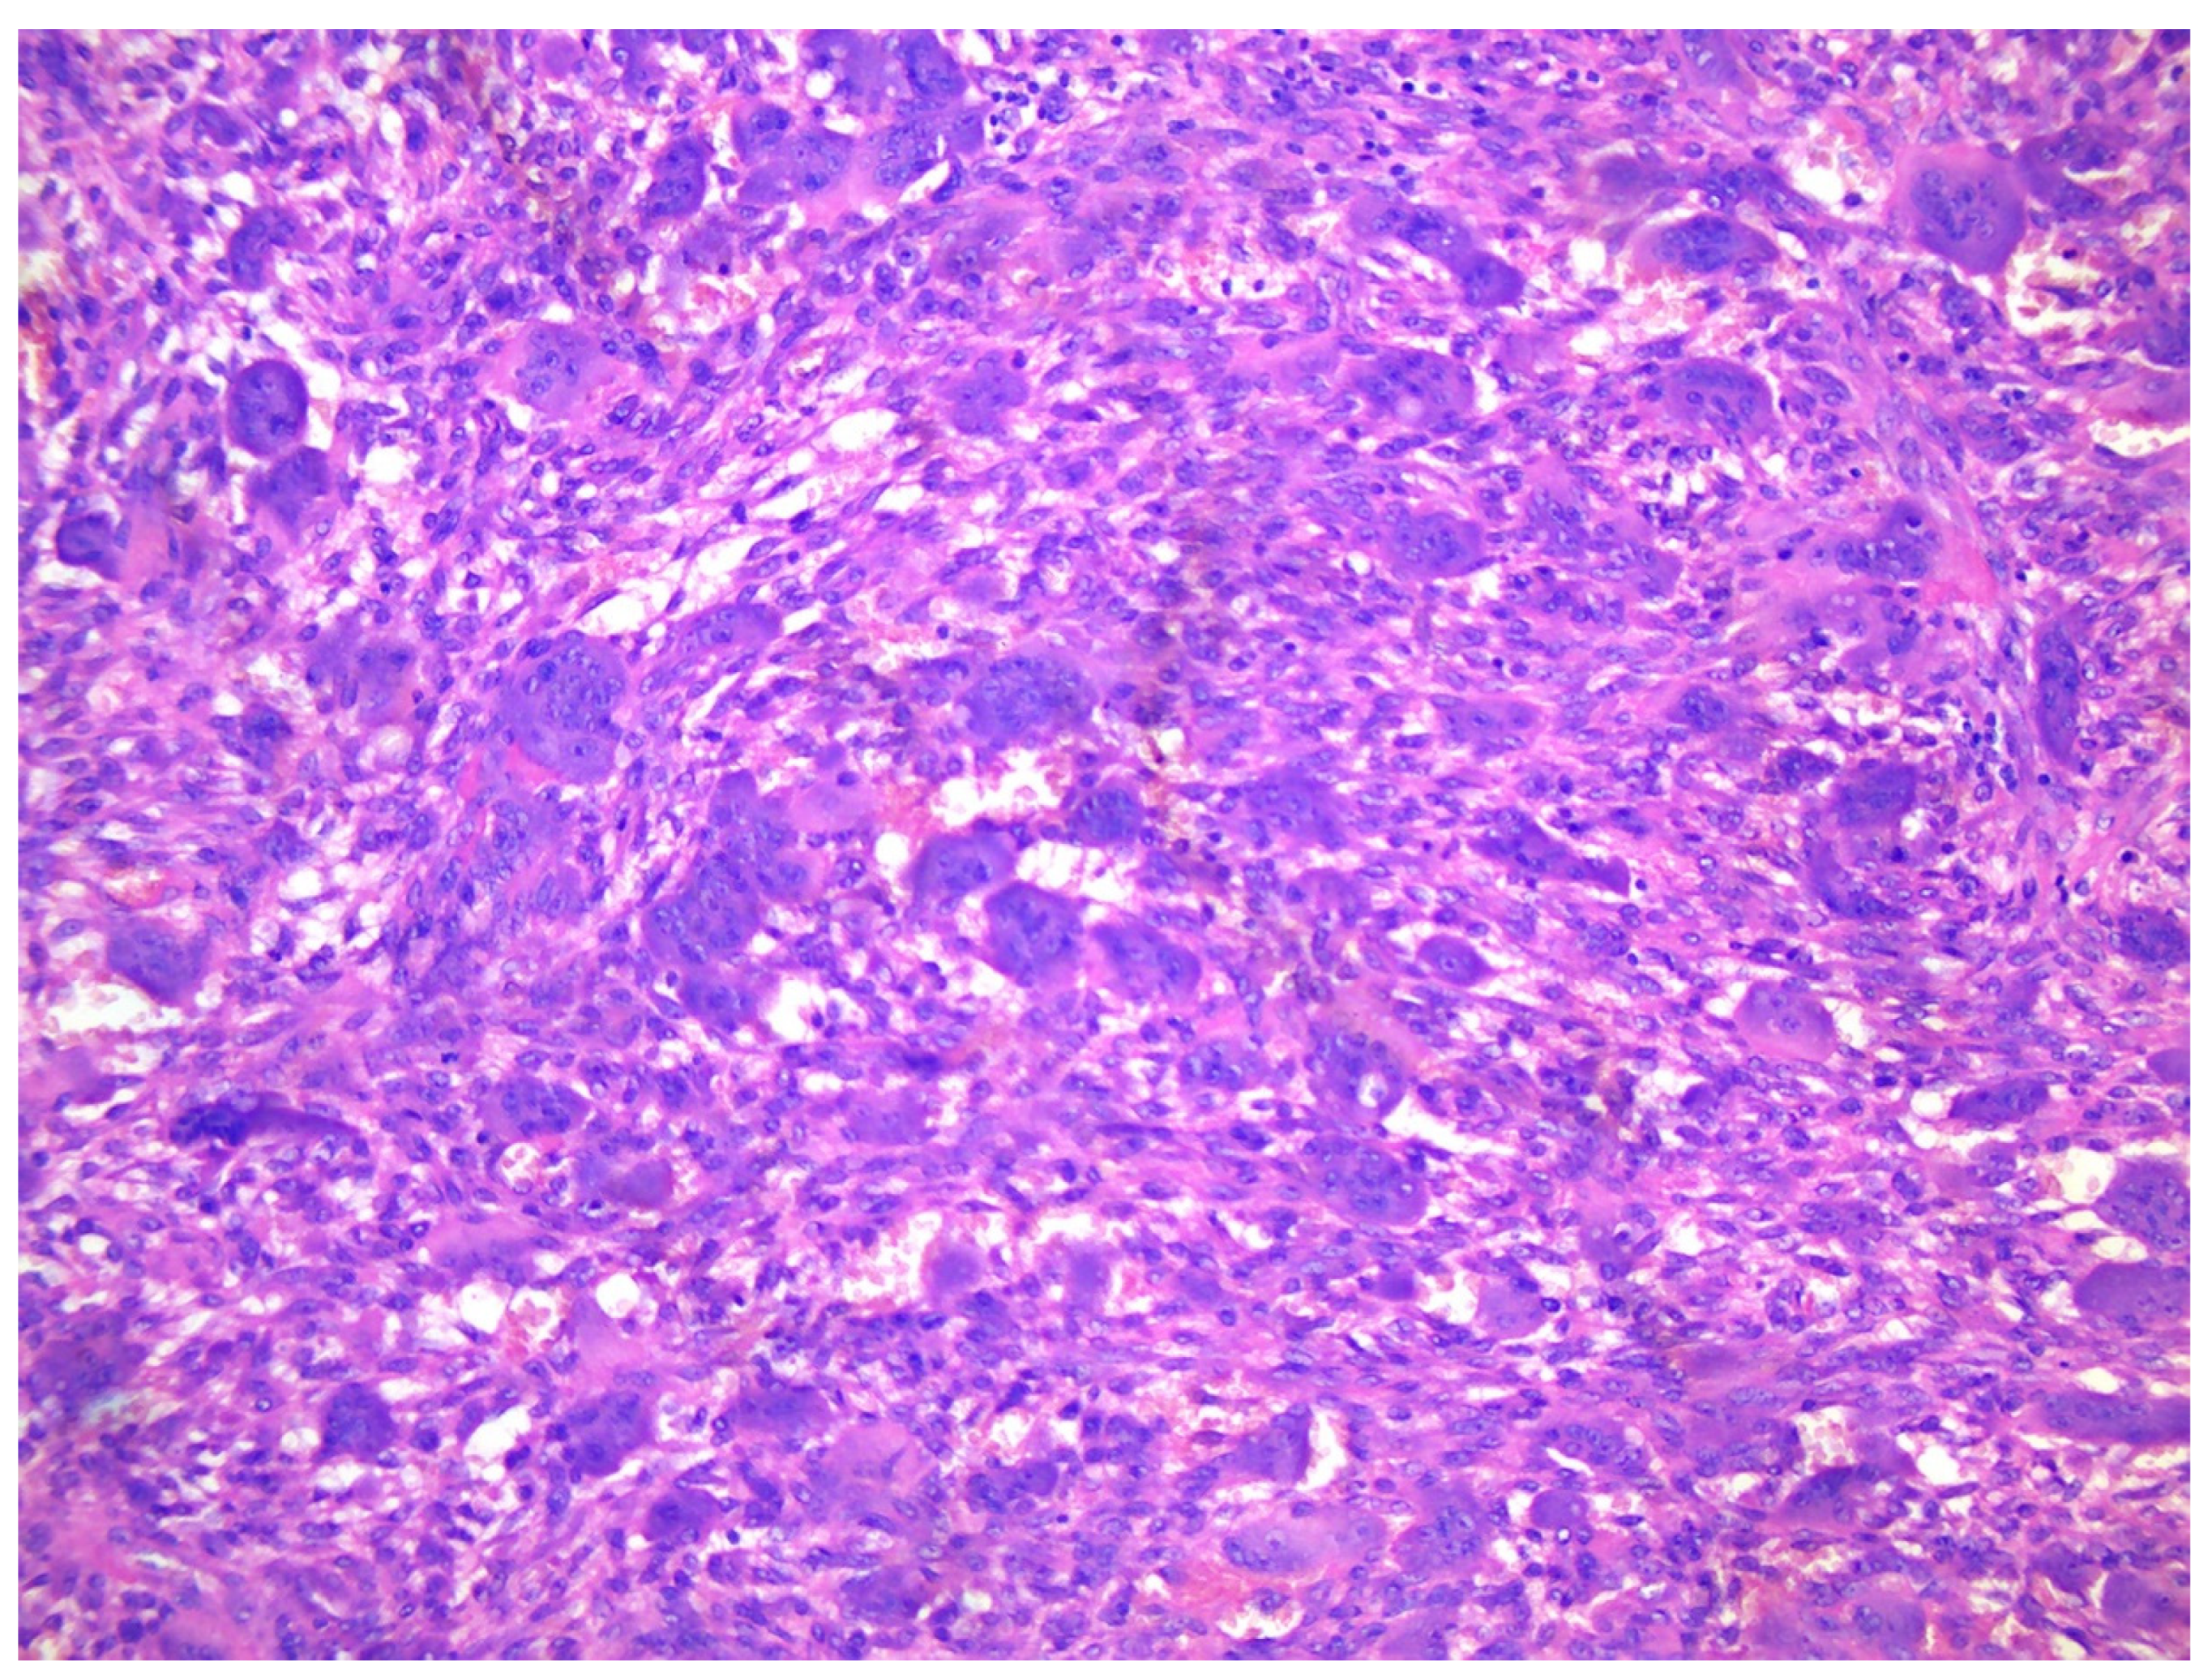

Figure 3. A. X-ray of a 70-year-old female showing two diaphyseal cortical radiolucency’s with a thick radiopaque inner margin. B. Histology of a typical brown tumour associated with hyperparathyroidism showing scattered multinucleated osteoclasts in a slightly storiform arranged background of spindled and rounded pre-osteoclasts.

A core needle biopsy is the gold standard for the diagnosis of fibrosa cystica osteitis and Brown Tumour.54 The fine needle biopsy (aspiration cytology) may suggest OFC appear as ossifying fibroma displaying spindled neoplastic cells producing trabecular bone and cementoid areas.55–57 Brown Tumours are highly vascularized lesions, histologically characterized by increased -often clustered - osteoclastic activity, haemorrhage, fibrosis, and reactive woven bone formation.55,56 In a Brown Tumour, the degradation of red blood cells will appear as brown pigment as the result of an accumulation of hemosiderin.55,56 The histological differential diagnosis of Brown Tumour includes giant cell Tumour of bone, giant cell reparative granuloma, or solid aneurysmal bone cyst. Clinical details include blood chemistry, radiological examination, and eventually FISH for USP6 rearrangements or immunohistochemistry for H3F3AG34 mutated protein.58